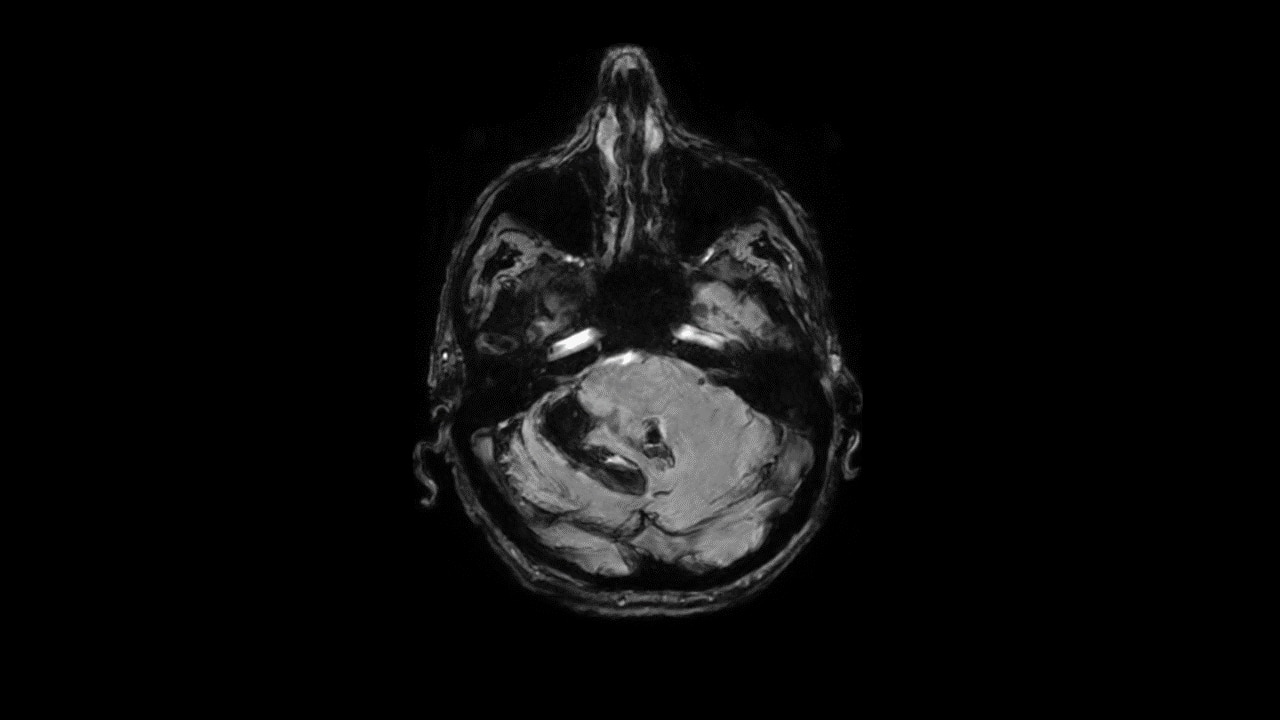

SWAN helps delineate small blood vessels, microbleeds, and large vascular structures in the brain. It applies a multi-TE readout technique that generates more than double SNR and is inherently less affected by the chemical shift compared to conventional SWI techniques. Whole brain acquisition with 3D, sub-millimeter resolution takes ~4 minutes—image reconstruction is virtually instantaneous.